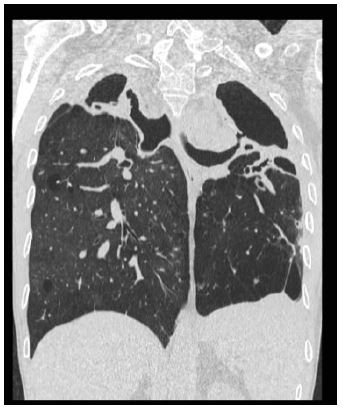

A PET/CT scan showed a significant accumulation of tracer in the lungs and vertebrae. MRI of the spine was permormed, that showed signs consistent with spondylodiscitis extended from D6 to D10 (Figure 2).

In the suspicion of a vertebral localization of atypical Mycobacteria found in the broncho-alveolar lavage (Ziehl-Neelsen positive staining with Koch Bacillus CRP negative) we performed a vertebral biopsy with detection of Mycobacterium Avium [2,3].

We have therefore confirmed the diagnostic suspicion of “Non-Tuberculosis Mycobacterial Lung Disease complicated by extensive spondylodiscitis".

Figure 2: (spondylodiscitis extended from D6 to D10).